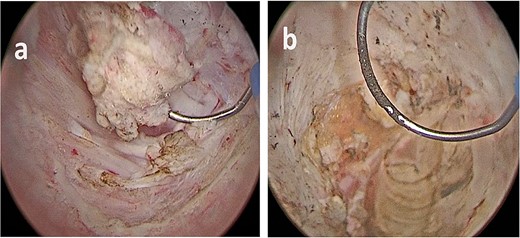

(a, b) Bladder lesion appearing as a nodular intravesical mass, in contrast with typical urothelial bladder cancer, which are commonly endoluminal.

The lesion appeared different from a typical urothelial bladder cancer (Fig. 3). The total operative time was 55 minutes, no postoperative complication occurred, there was no postoperative pain, and the patient was discharged 2 days later.